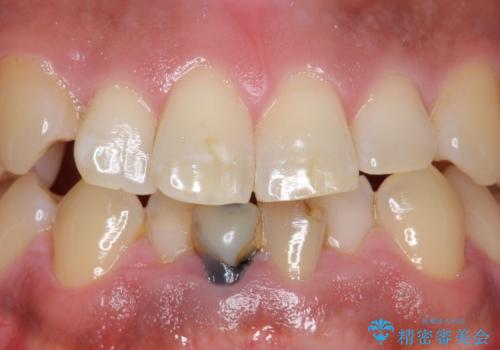

奥歯がズキズキ痛い 根管治療

担当医 河口智英